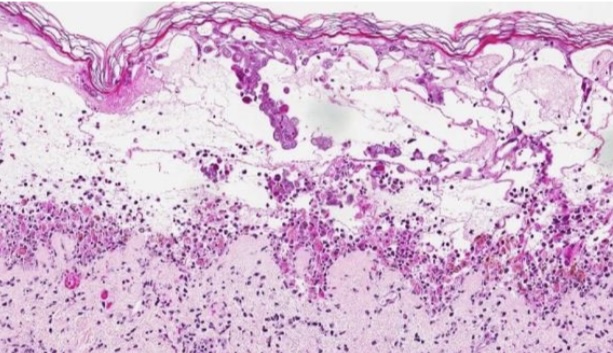

Ballooning degeneration

Hydrophic degeneration

Cell swelling